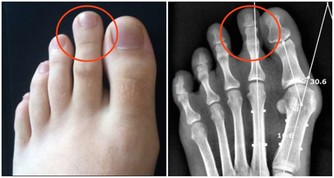

痛風:洋蔥泡紅酒

洋蔥去皮切開泡紅酒,放在冰箱冷藏一周,飲用吃蔥,對痛風也很有幫助。